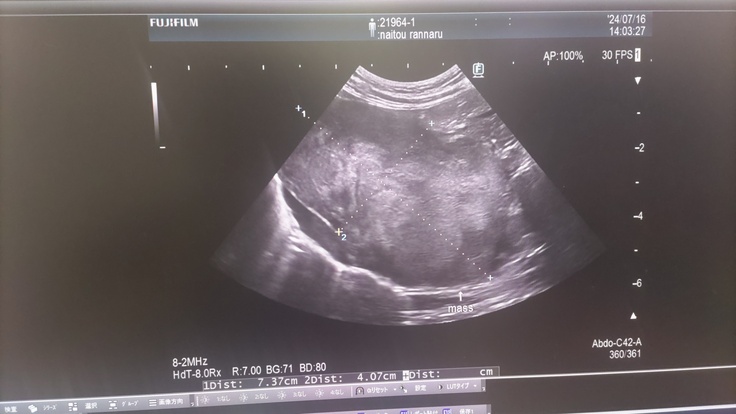

超音波検査で肝臓にも腫瘍が見つかったこと。恐らく胸のリンパ腫から転移したと思われるが、こちらも共に検査機関に送ったこと。

肝臓の腫瘍 約7cm×4cmの巨大腫瘍 写真中央の十字点線で示しているのが腫瘍です

左の写真が現在の肝臓の腫瘍(ほぼ無し)、

右の写真が7/15の時の腫瘍(7cm×4cm)